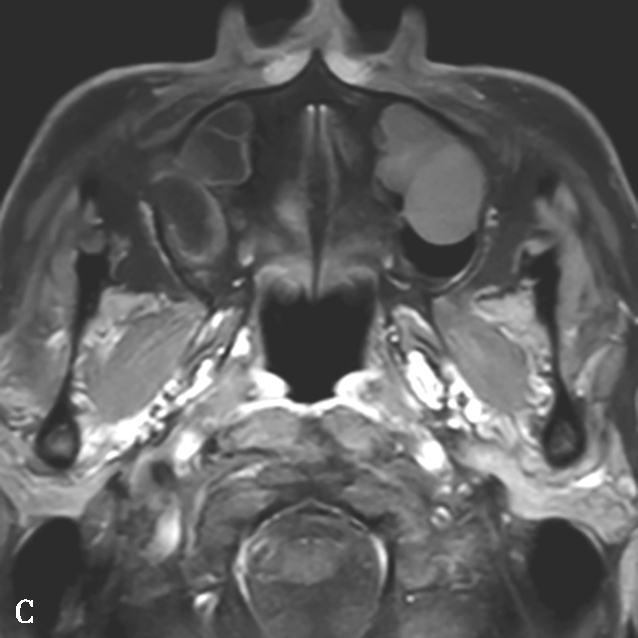

1.CT表现

该病息肉样变及水肿通常发生于中鼻甲周围,即病变大多位于前组筛窦、后组筛窦以及嗅裂区,表现为以筛窦为主的高密度影。呈典型的“双重密度”表现,即受累鼻窦腔内斑片状或云雾状高密度影,其中高密度影对应嗜酸性黏蛋白(eosinophilic mucin,EM)的位置,周围低密度影为水肿的鼻窦黏膜(图1-3-24A、B)。

2.MRI表现

EM表现为T 1 低信号或中等信号,T 2 极低信号或信号缺失(图1-3-24C~E)。

图1-3-24 嗜酸细胞增多黏液性鼻窦炎

A、B.横断面及冠状面CT骨窗,示双侧额窦、筛窦、上颌窦及蝶窦腔充填软组织影,密度不均匀,见多发斑片状磨玻璃样密度影“双重密度影”;双侧中、总鼻道见软组织影充填;C~E.横断面T 1 WI、T 2 WI及冠状面T 1 WI,示全组鼻窦窦腔充填长T 1 、混杂短到长T 2 信号影,双侧中鼻道、总鼻道及上颌窦窦口区可见小斑片状略短T 1 混杂等到短T 2 信号影